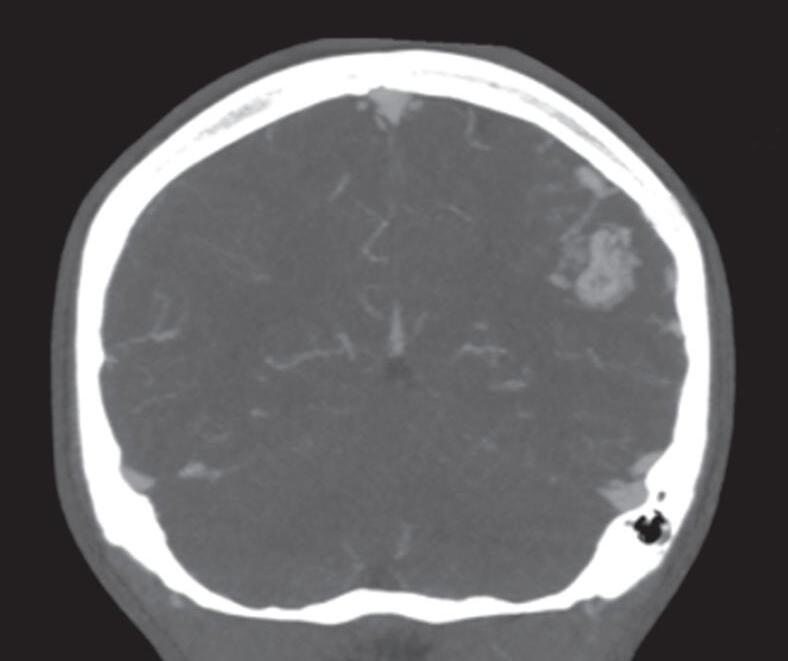

A suspeita diagnóstica das MAVs geralmente é feita por meio de métodos não invasivos de aquisição de imagem, tais como tomografia computadorizada (TC), angiotomografia, ressonância magnética (RNM) e angiorressonância, contudo, as informações anatômicas vasculares necessárias para o planejamento e a execução terapêutica demandam geralmente do estudo dinâmico da angioarquitetura da MAV pela arteriografia cerebral, considerado o exame padrão-ouro para o diagnóstico (Figs. 1-21 e 1-22).35

Em virtude de as manifestações clínicas não serem exclusivas das MAVs, a tomografia computadorizada do crânio sem contraste

é geralmente o primeiro exame realizado na investigação diagnóstica. Algumas alterações presentes nessa tomografia, associadas à história clínica do paciente podem direcionar a suspeição diagnóstica; são eles: pacientes jovens com hemorragia intraparenquimatosa lobar espontânea, sangramento inexplicável intraventricular ou subaracnóideo, presença de calcificações curvilíneas ou salpicadas, ou imagens serpiginosas espontaneamente hiperdensas, que podem corresponder a vasos anômalos integrantes do nidus, a veias de drenagem ou a artérias nutridoras dilatadas. Embora a angiotomografia possibilite uma melhor visualização das estruturas vasculares, a ressonância magnética em contrapartida, permite melhor

Fig. 1-21. TC de crânio sem contraste em cortes (a) axial e (b) coronal. (c) RNM encéfalo T1 com contraste axial. (d) Angiorressonância arterial sagital. Arteriografia digital em (e) AP e (f) perfil, demonstrando MAV não rota localizada no giro pré-central à esquerda nutrida por ramos da artéria cerebral média e caloso marginal esquerdo. Setas azuis apontando para o nidus da MAV.